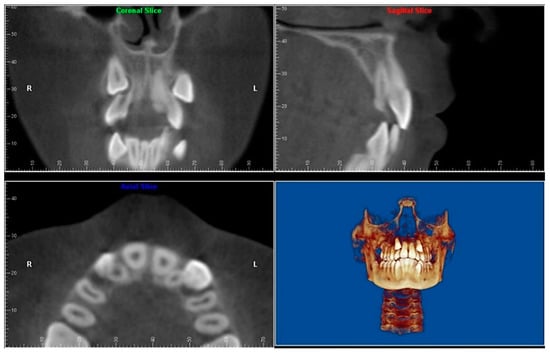

- Evaluation of buccal and lingual cortical plates: Figure 5, Figure 6 and Figure 7 show a case in which the mandibular lateral incisors are positioned lingual to the central incisors. Both mandibular lateral incisors are adjacent to each other. Figure 5 shows and intraoral occlusal photos with retained deciduous mandibular lateral incisors. There was no way to evaluate the buccal and lingual cortical plates through conventional 2D panoramic, periapical or occlusal radiographs. Therefore, CBCT was acquired and collimated to the area of teeth in order to assess the relationship of the four mandibular incisors to the labial and lingual cortical plates as well as to the adjacent teeth. As Figure 6 and Figure 7 display, CBCT shows that all permanent mandibular incisors are sound. It is important to note that thin buccal and lingual cortical plates may not be seen via CBCT—this does not denote that they are not present. In other words, CBCT images may not show a clinically present thin buccal and lingual cortical plates. In this case, the diagnostic information obtained from CBCT is far more significant than the information obtained from any other radiographic imaging technique.